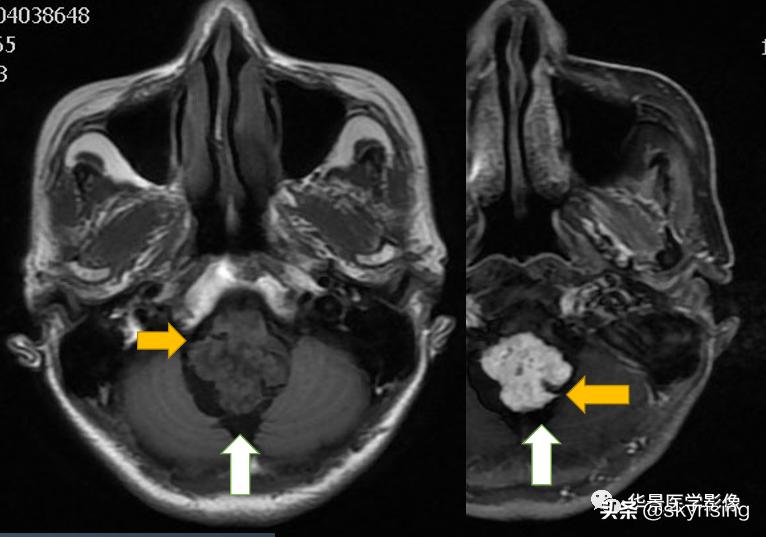

上图白色箭头:小脑延髓池内延髓背侧不规则形团块影,延髓受压变形。

黄色箭头:走行与病灶边缘的流空信号血管影。

上图白色箭头:小脑延髓池内延髓背侧不规则形团块影,小脑半球、延髓、第四脑室受压变形,所见诸脑室未见增宽。

蓝色箭头:延髓受压前后径变窄,T1信号减低,考虑合并水肿。

黄色箭头:病灶边缘见流空信号血管影。

小脑延髓池内见不规则异常信号影,呈长T1长T2信号,内部信号不均,边缘见稍粗大流空信号血管影,FLAIR少许片状低信号,增强呈明显强化,DWI不均质低信号,ADC不均质高信号。小脑半球、延髓、第四脑室受压变形。临近延髓变窄,呈长T1长T2信号。

总体以不规则实性占位病变,临近走行血管流空信号影,增强明显强化,DWI低信号为特点。